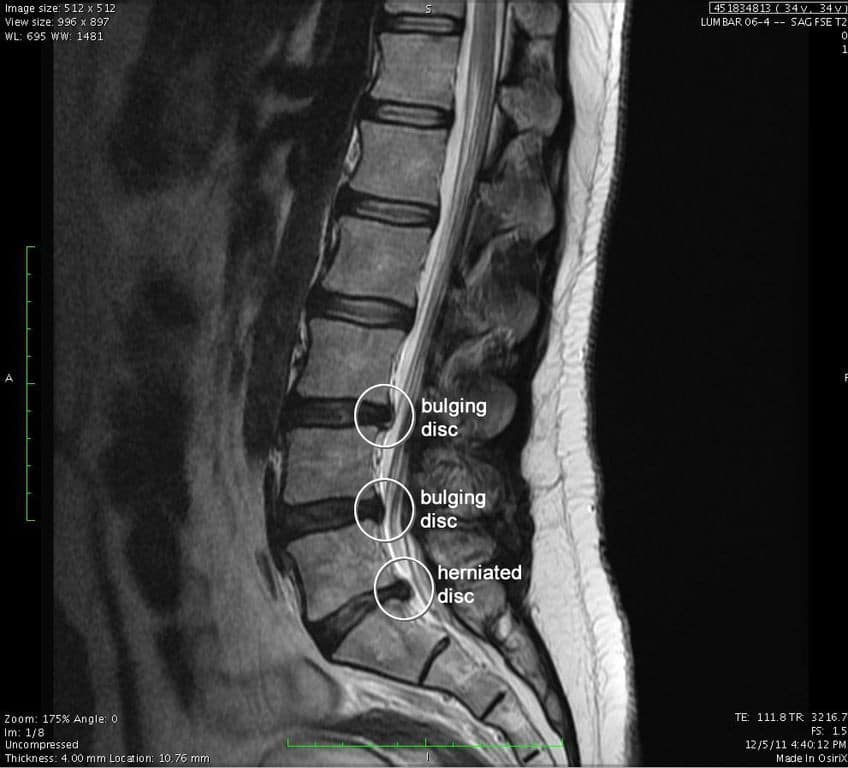

bulging-disc.jpeg

You’ve had chronic low back pain for months and/or years. Your doctor ordered you an MRI which showed multi-level degeneration/ arthritis, bulging or herniated disk(s), stenosis, or another long terrifying word. You were told you the treatment options were steroid or an epidural injection, NSAIDs, opioids, physiotherapy or even to consult a neurosurgeon. You may have been told that you have to live with this pain. You tried a few of those treatment options with no success or the success (pain relief) was short lived. This left you disheartened, depressed and thinking that you are going to be in pain for the rest of your life. You now avoid physical activity because you think or have been told that it will make your condition worse.

Sound familiar? I hear various versions of this story on a daily basis during my initial consultations. While MRI and other diagnostic imaging remains an excellent assessment tool, it unfortunately carries the burden of giving patients a beautiful mental image of ‘how bad their injury is’ and can contribute to negative thoughts about recovery and prognosis. (Wang et al., 2018)

What if I told you that asymptomatic individuals (people without pain or other symptoms of disease/condition) can have the same CT/ MRI findings as you?

A study conducted by Brinjikji, et al. (2015), systematically reviews the evidence for the prevalence of common spine conditions on asymptomatic people through decades of age: 20, 30, 40, 50, 60, 70, and 80 y/o. The goal of this study was to estimate the prevalence of common spine conditions which showed on diagnostic imaging of healthy individuals (asymptomatic). This study reviewed 33 articles reporting  imaging findings for 3110 asymptomatic individuals.

What does this mean for you?

This study proves that some findings are part of the normal aging process and may be unassociated with low back pain. In short, your pain MAY NOT be stemming from what shows up on diagnostic imaging reports!  It is our job as your healthcare providers to make a clinical judgement based on our assessments, the patient history and diagnostic imaging to figure out exactly what is MOST LIKELY causing your pain and then discuss your treatment options. In many cases, you DO have conservative treatment options and likewise, the worst thing many patients can do is avoid any type physical activity. Of course, in some circumstances the diagnostic imaging does help us determine the source of your pain, it also helps us better understand what is going on in your spine, what we can expect in terms of recovery, and what is the best available options for your unique circumstance.

We as healthcare practitioners NEED to do a better job of educating the patient about the findings and how they correlate to their pain. We also need to do a better job of not basing a diagnosis solely on diagnostic imaging.